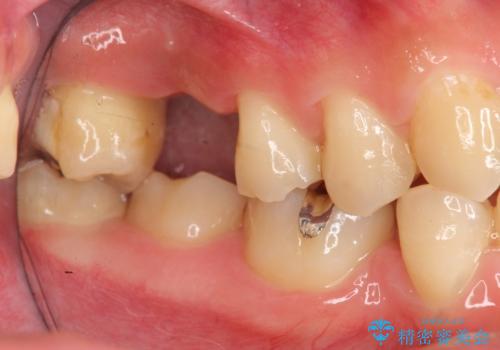

ソケットリフトを伴うインプラント補綴

- 右上の歯を喪失し機能回復を希望され来院されました。

骨量が不十分であった為、ソケットリフトを併用しインプラントによる補綴計画を立てます。